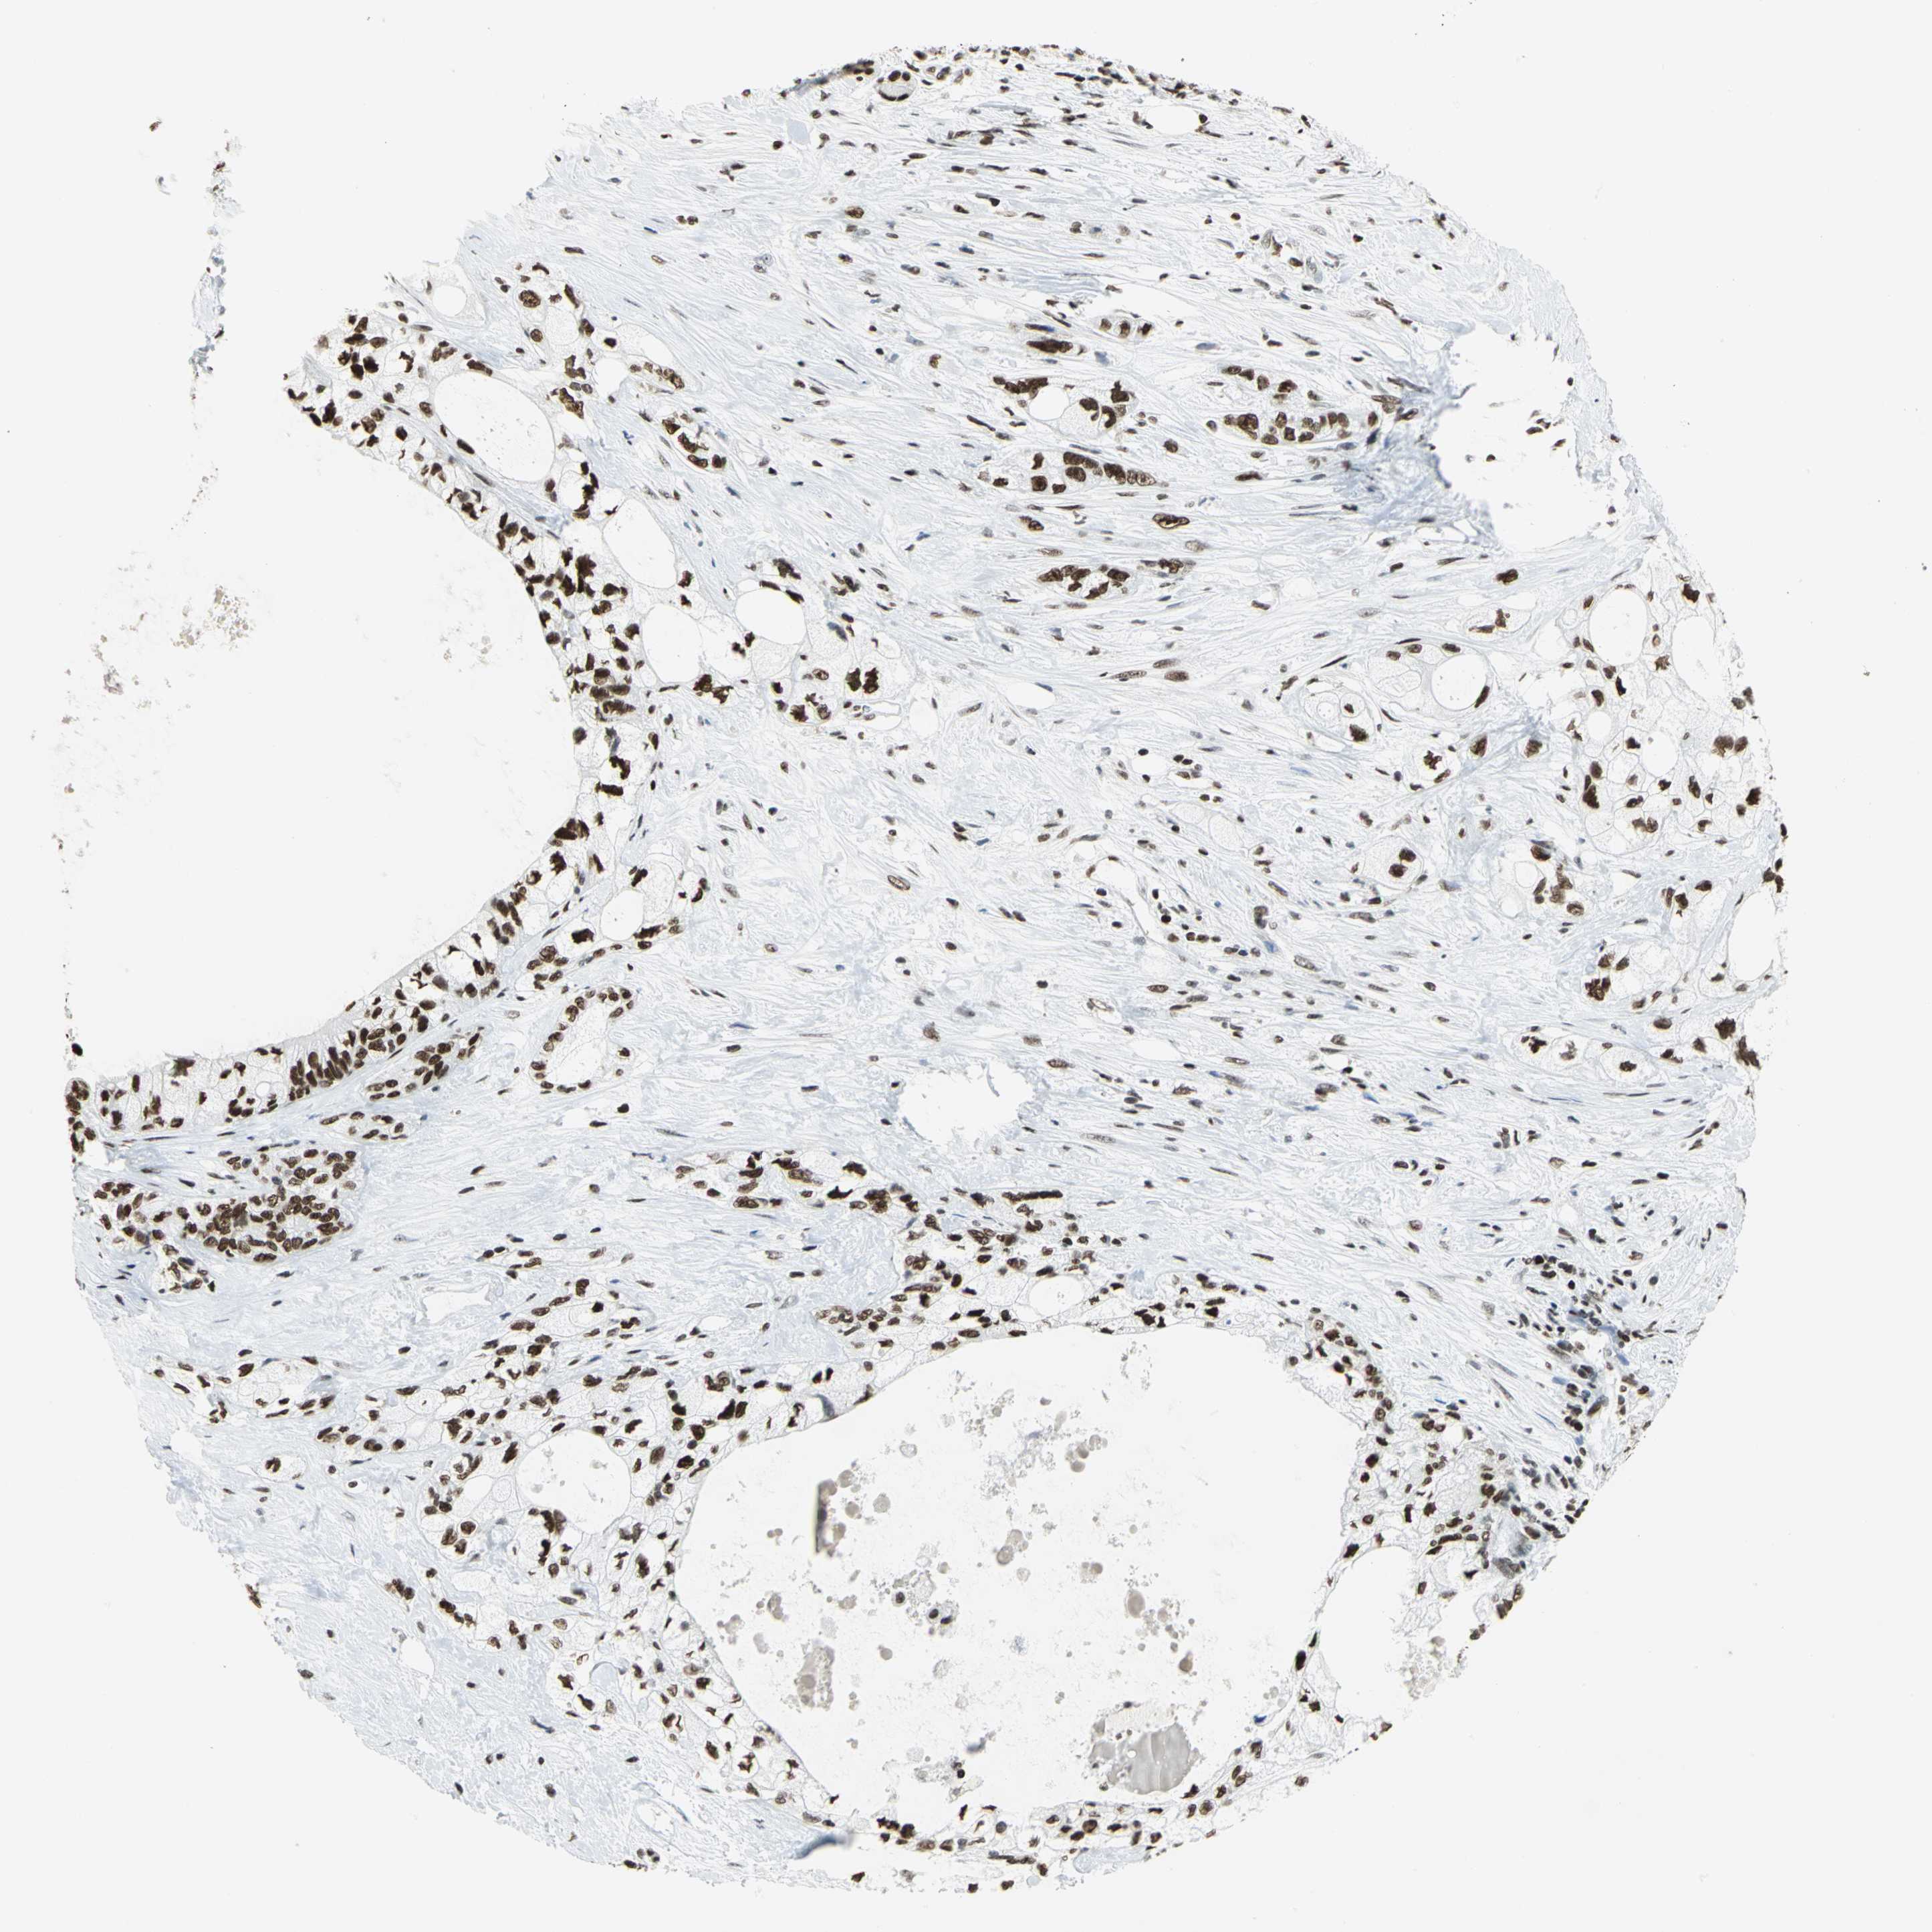

PANCREATIC CANCER - Protein expressioni

A mouse-over function shows sample information and annotation data. Click on an image to view it in a full screen mode. Samples can be filtered based on level of antibody staining by selecting one or several of the following categories: high, medium, low and not detected. The assay and annotation is described here.

Note that samples used for immunohistochemistry by the Human Protein Atlas do not correspond to samples in the TCGA dataset.

Antibody stainingi

Antibody staining in the annotated cell types in the current human tissue is reported as not detected, low, medium, or high, based on conventional immunohistochemistry profiling in selected tissues. This score is based on the combination of the staining intensity and fraction of stained cells.

Each image is clickable and will lead to virtual microscopy that enables deeper exploration of all samples and also displays staining intensity scores, fraction scores and subcellular localization as well as patient and tissue information for each sample.

Antibody HPA003506

Antibody CAB005873

Staining

High

Medium

Low

Not detected

Intensity

Strong

Moderate

Weak

Negative

Quantity

>75%

75%-25%

<25%

None

Location

Nuclear

Cytoplasmic/membranous

Cytoplasmic/membranous,nuclear

Adenocarcinoma, NOS

Adenocarcinoma, metastatic, NOS